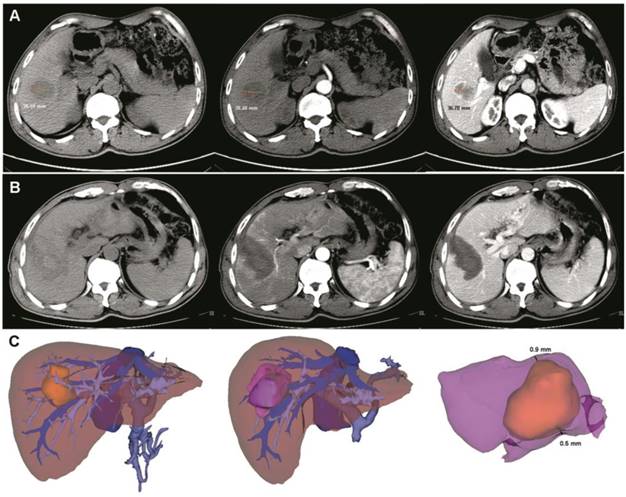

An image fusion system (Myrian-Xp-Live software), as described in our previous study [9], was used to evaluate the RFA safety margin at 1 month after surgery. Images of the ablation area and tumor were superimposed in a 3D model (Figure 1). The transparency of two models (per- and post-RFA) were adjusted and rotated to determine and measure the shortest tumor-free margin. A safety margin of 5 mm or more was considered as complete ablation, while less than 5 mm was considered as incomplete ablation [9].

Pre- and post- operative 3D-CT reconstruction and image fusion. (A) Pre-operative two-dimension computed tomography (plain scan, arterial and venous phases). The tumor size was about 38.59 mm. (B) After ultrasound-guided RFA combined with 3D-CT reconstruction, a low-density area was observed (plain scan, arterial and venous phases). (C) Pre- and post-operative 3D-CT reconstruction and image fusion. The yellow mass indicates the tumor and the purple mass indicates the ablation area. After image fusion, the safety margin was measured in a multidimensional approach. In this case, the thinnest safety margin was 0.6 mm. RFA, radiofrequency ablation.